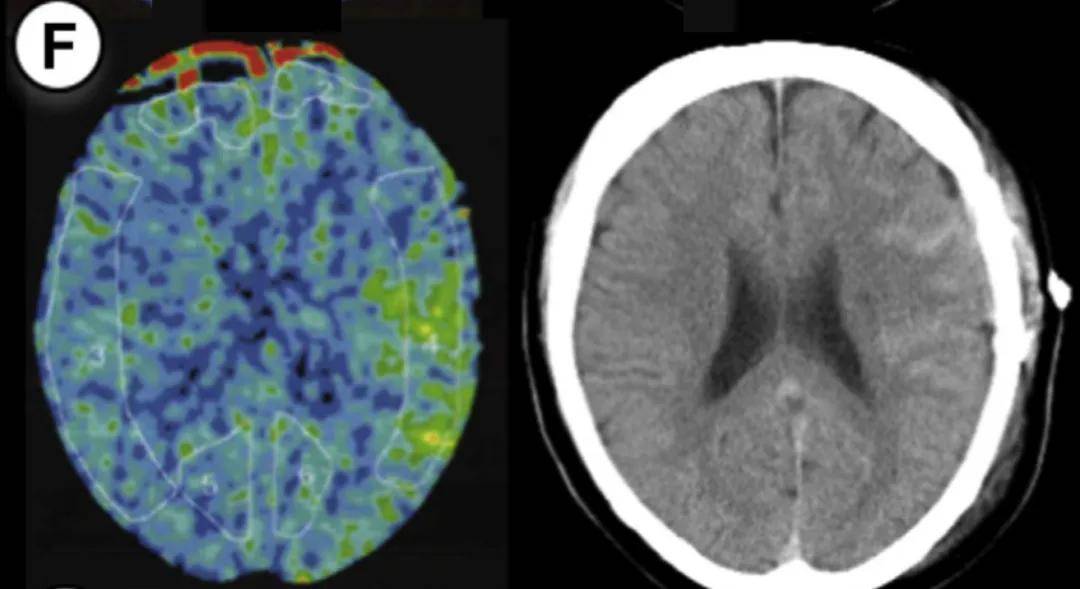

病例1:55岁男性,右侧大脑手术。方法1 rCBF增加率47%,方法2达55%(超过50%阈值)。术后第3天未维持镇静,第2天发生脑出血,改良Rankin量表评分恶化。

病例2:55岁男性,左侧大脑手术。方法1和方法2的rCBF增加率均为50%,达到预警阈值。术后第1天发现少量蛛网膜下腔出血(SAH),因术前规划2天镇静和血压控制,未出现神经功能缺损。

病例3:44岁女性,左侧大脑手术。方法1 rCBF增加率100%,方法2达114%,术后第2天脑出血。因术后及时给予1天镇静和严格控压,未遗留神经功能问题。

病例4:49岁女性,右侧大脑手术。方法1 rCBF增加率89%,方法2达133%,术后第5天发现硬膜下血肿合并蛛网膜下腔出血。

病例5:49岁男性,左侧大脑手术。方法1 rCBF增加率78%,方法2高达149%,术后第2天发现少量蛛网膜下腔出血。术后给予1天持续镇静,出血未扩大。

病例6:26岁男性,右侧大脑手术。方法1 rCBF增加率63%,方法2达72%,术后第2天发现硬膜下血肿合并蛛网膜下腔出血。术后1天镇静干预后出血吸收。

病例7:35岁女性,左侧大脑手术。方法1 rCBF增加率77%,方法2达67%,术后第2天发现出血合并脑室内出血。因术前知晓rCBF超标,提前规划镇静干预。

7个病例年龄范围25-55岁(无儿童),出血类型包括脑出血(ICH)、蛛网膜下腔出血(SAH)、硬膜下血肿(SDH)及混合出血,发病时间术后1-5天。所有患者rCBF增加率均≥30%(方法1)或≥50%(方法2),证实这两个阈值的预警价值。

基于7例病例总结术后管理三步骤:

第一步:术后rCBF精准测量

通过氙气增强CT,在大脑中动脉供血区固定部位测量rCBF,术后即时完成首次检测。

第二步:分层干预方案

第三步:干预连续性保障

rCBF未降至安全范围前,不可擅自停止镇静或放松血压控制。